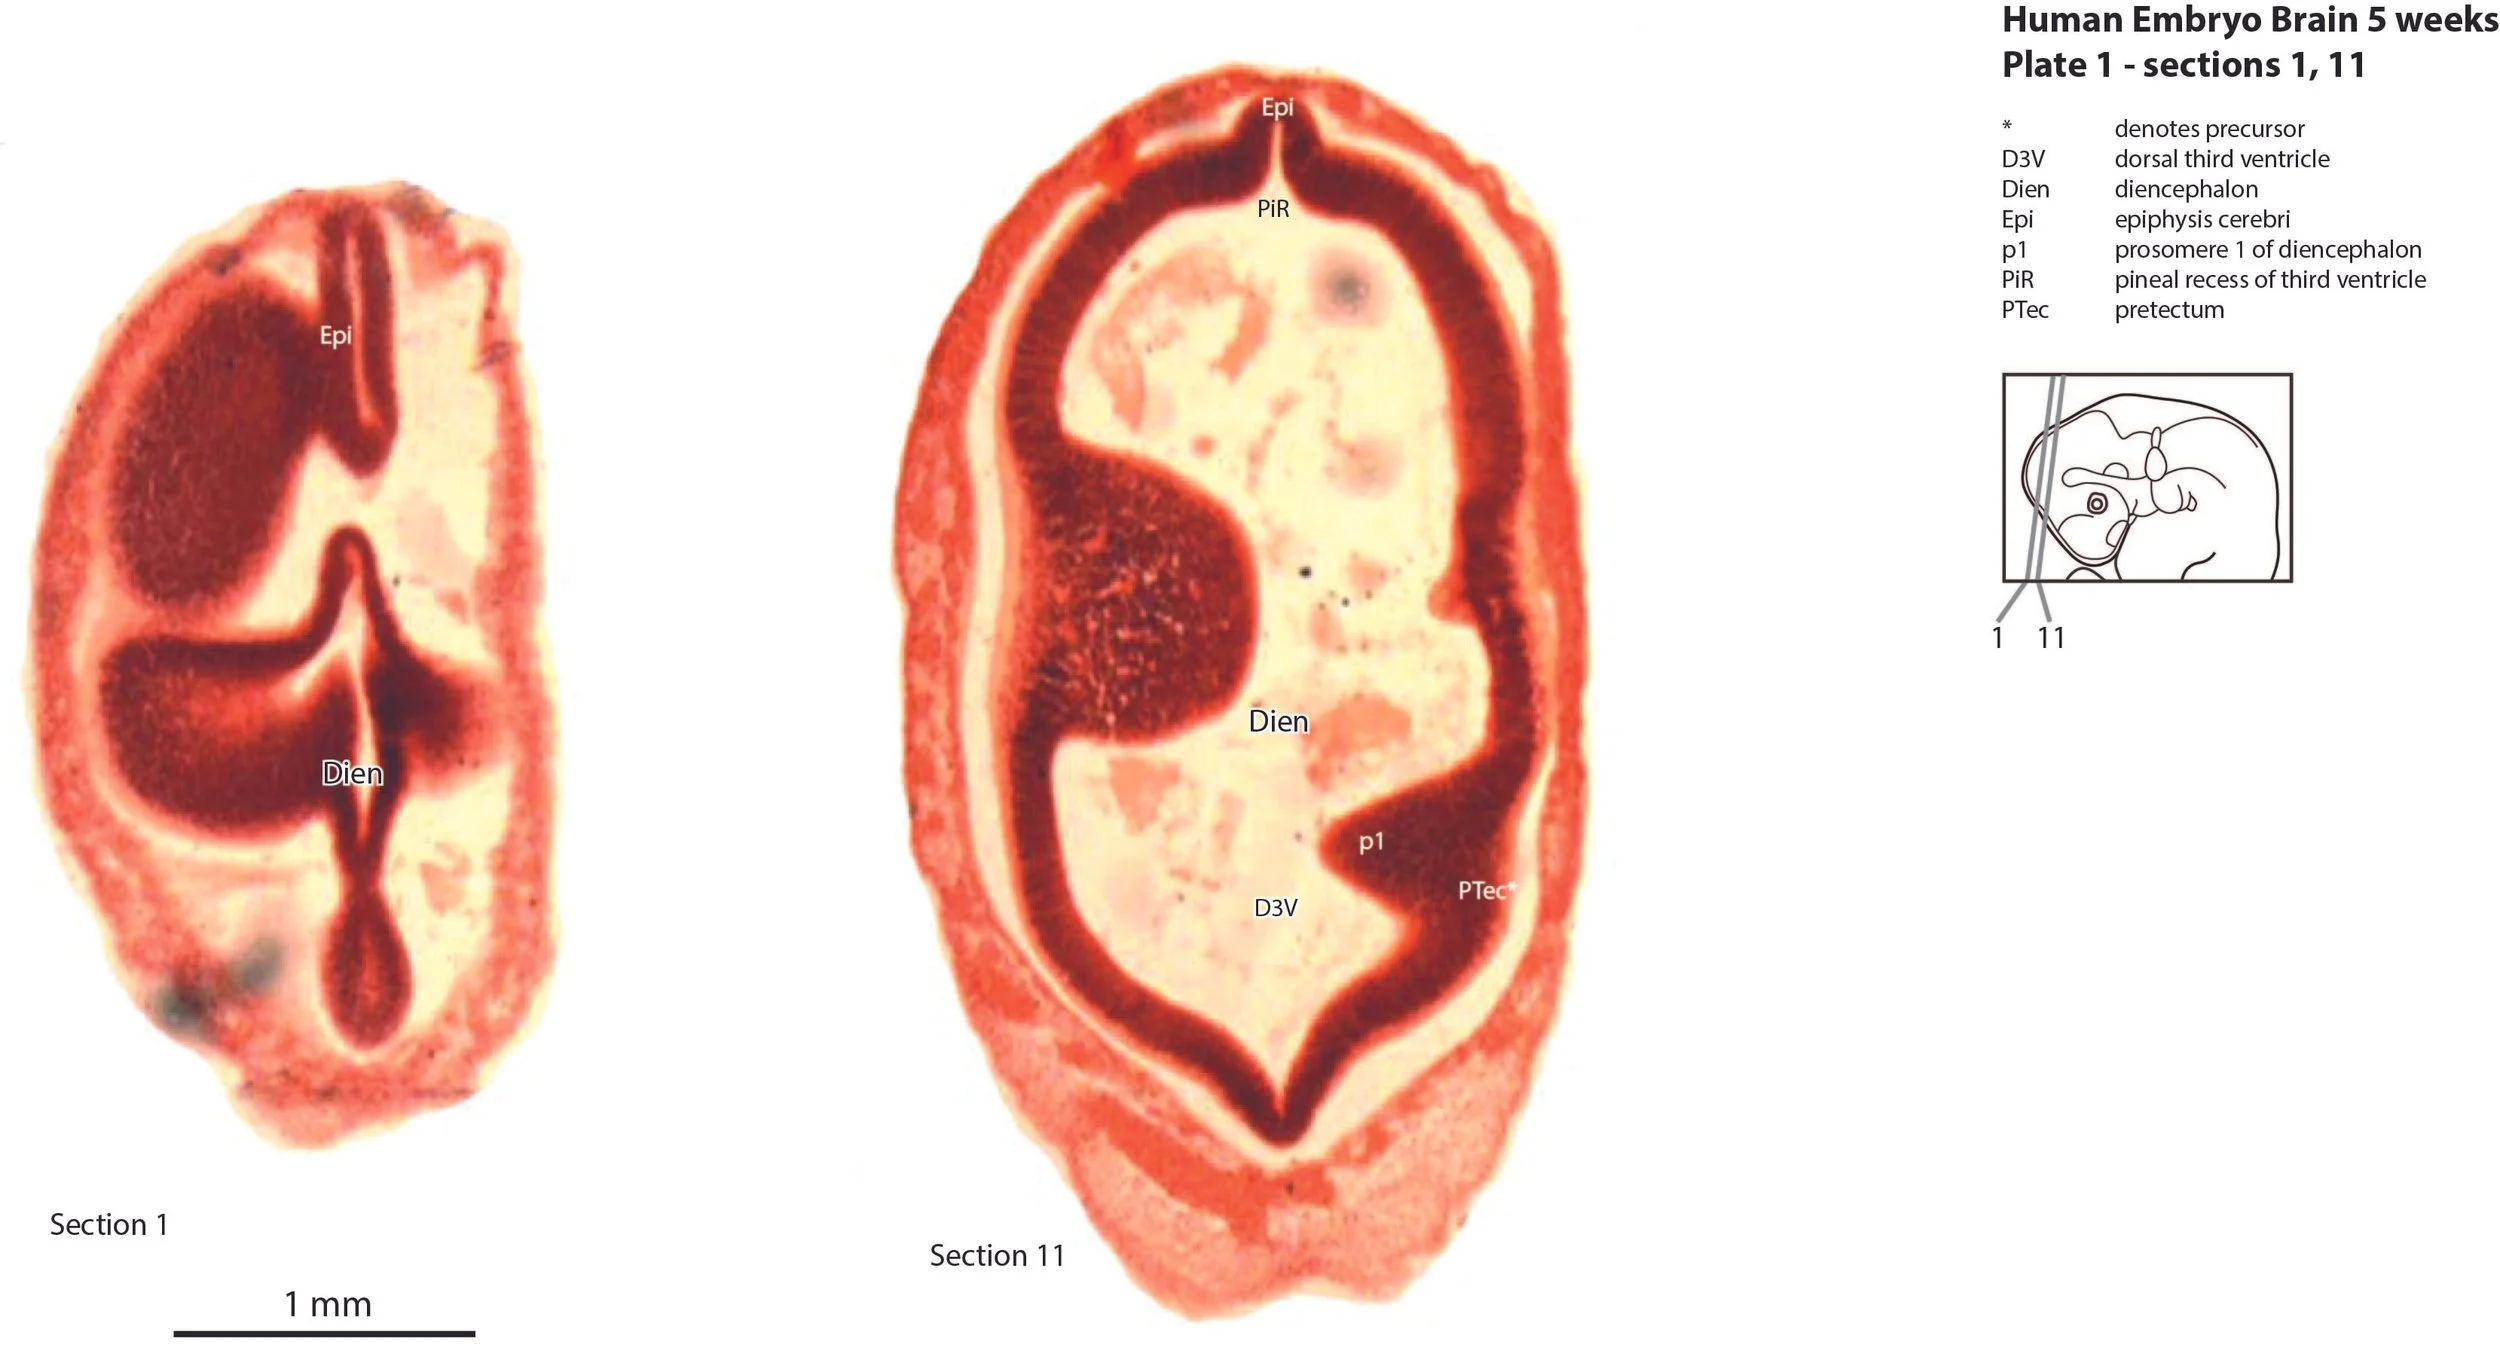

This specimen is at a stage when all five secondary brain vesicles have appeared, although the evagination of the telencephalic vesicles is incomplete.  The bulk of brain tissue is made up of proliferative compartments (neuroepithelium), with only very small populations of (post-mitotic) neurons in the rhombencephalic tegmentum.  Segmentation is visible in the forebrain into prosomeres (diencephalon), hypothalamic segments (hy1, hy2, hyat), pallium or protocortex and ganglionic eminences (telencephalon).

The diencephalon has the typical prosomeric structure.  Prosomeres 1 (pretectum), 2 (dorsal thalamus), and 3 (prethalamus) can be identified as proliferative zones (see plates 1 to 3), but postmitotic populations are negligible, particularly in the dorsal thalamus (Th in plates 2,3).